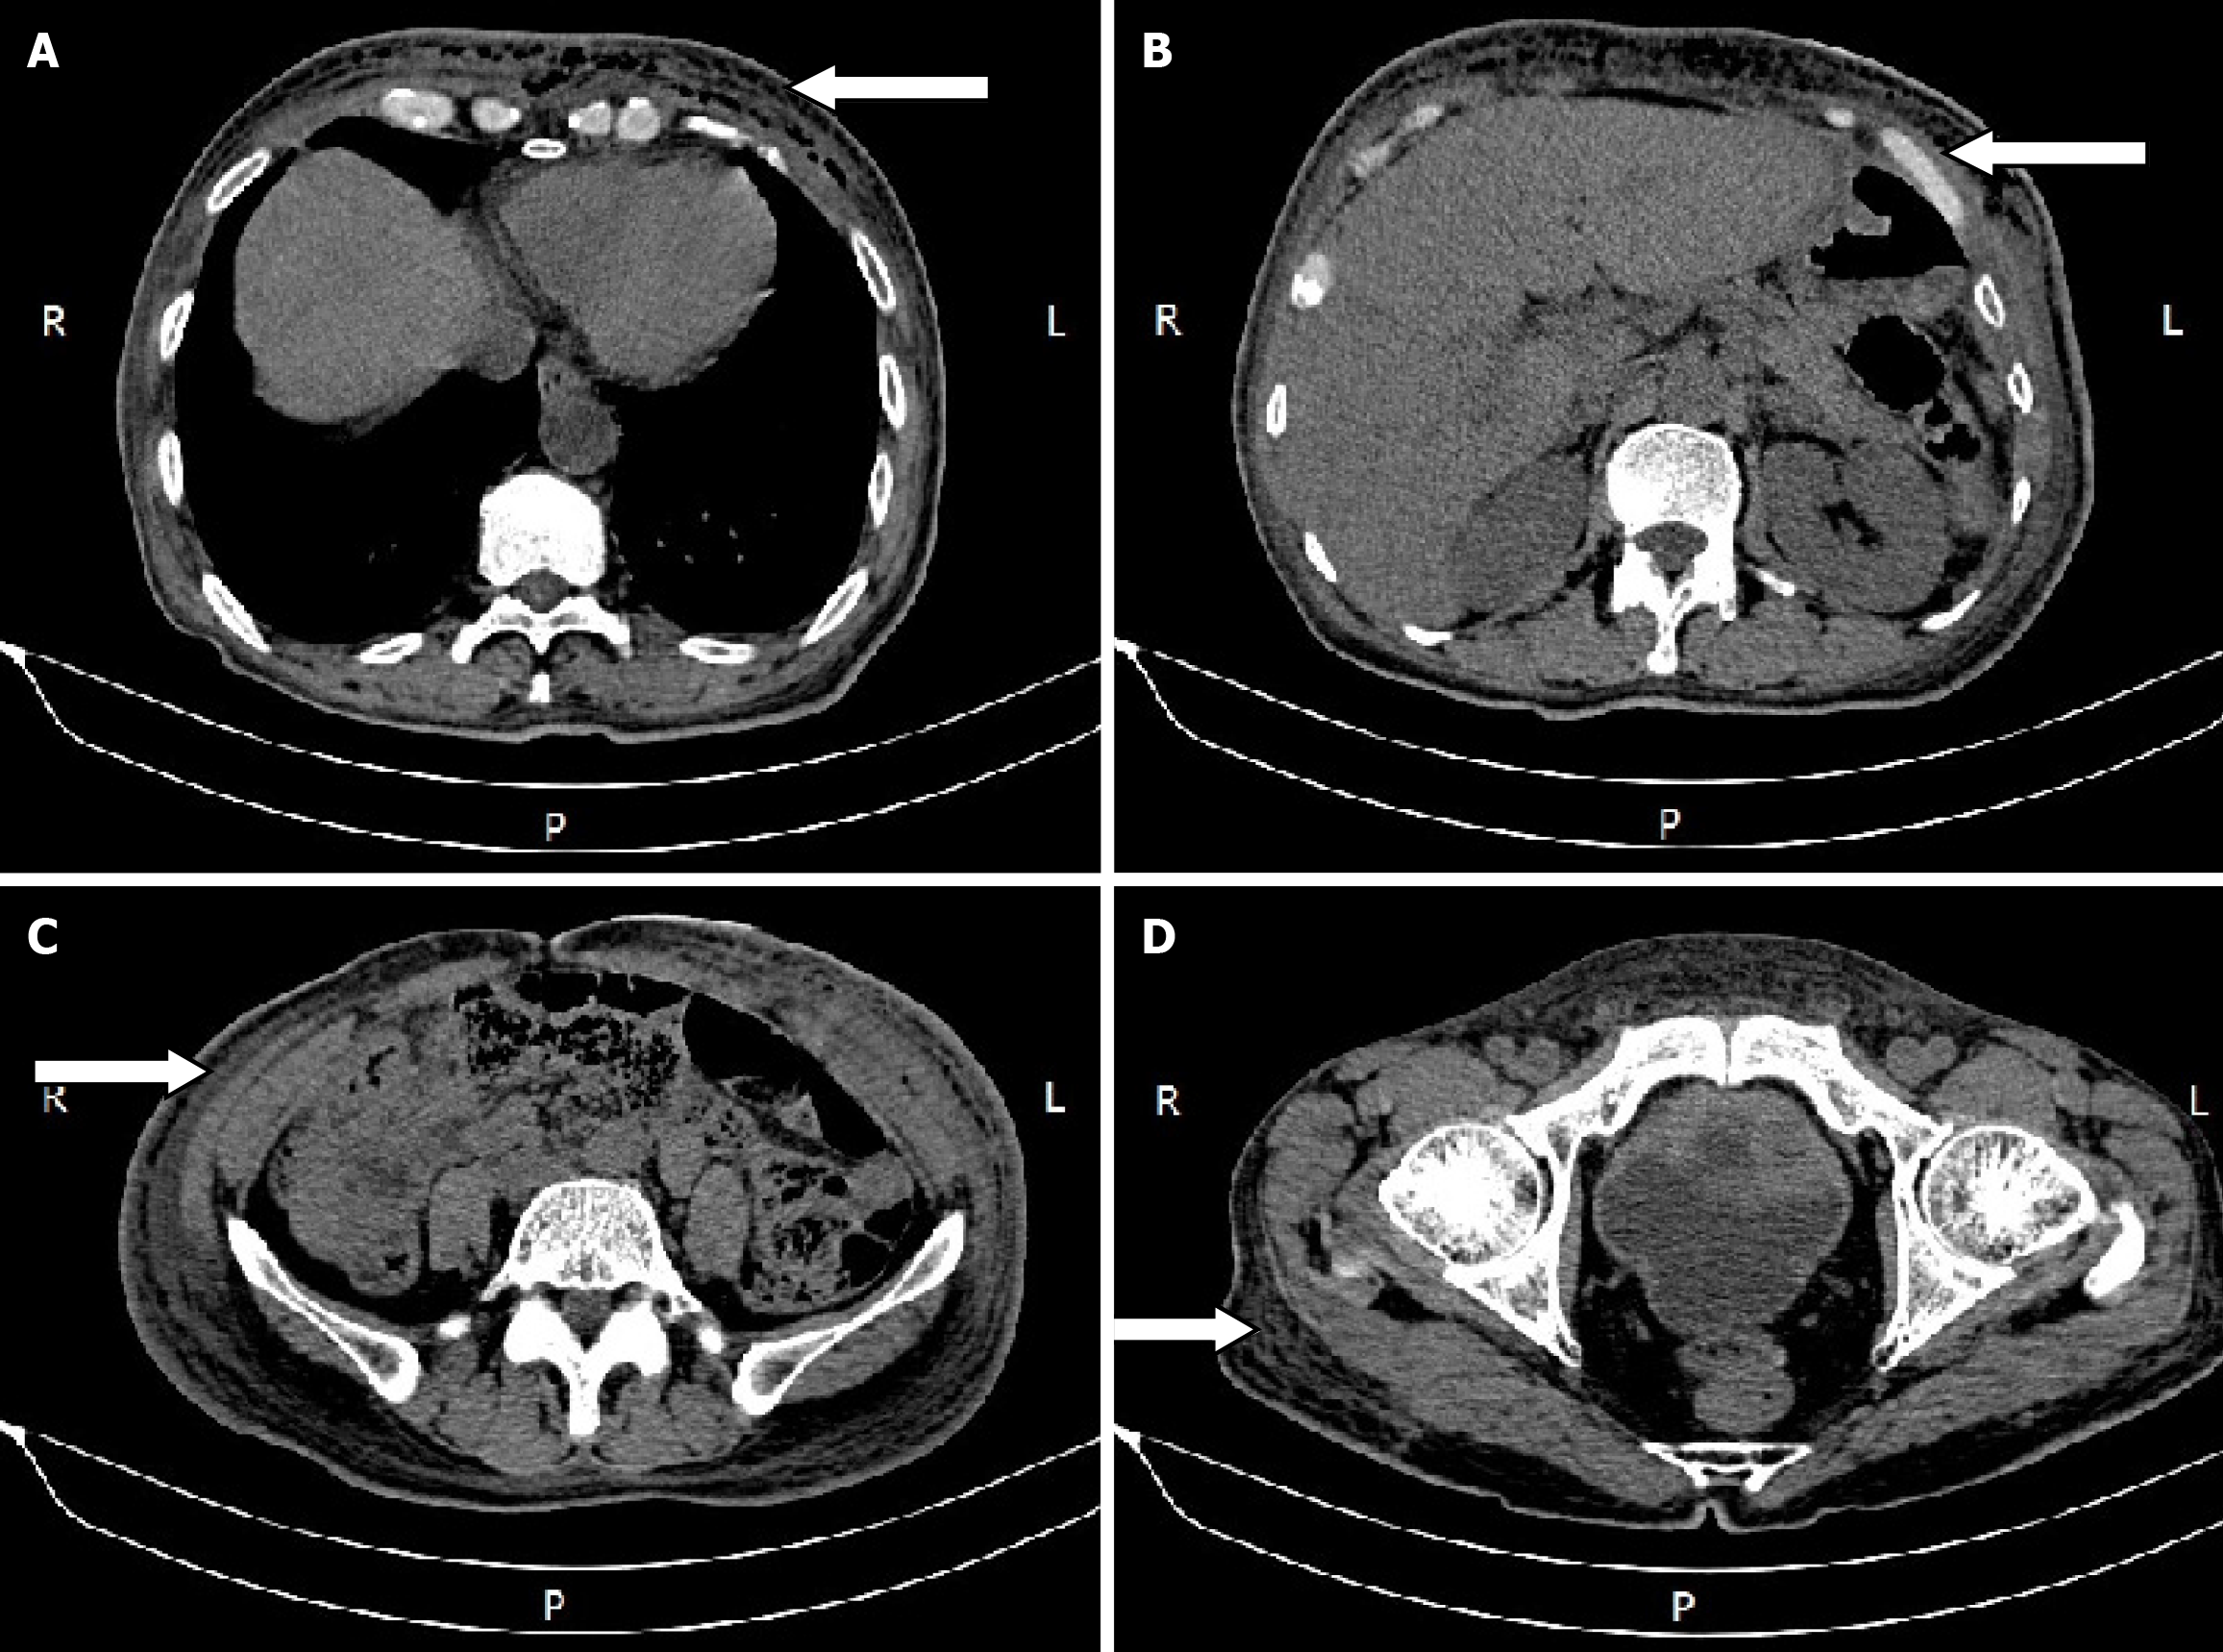

An abdominal computed tomography (CT) scan showed diffuse edema with pneumatosis of the antero-inferior chest wall and abdominal wall, and cellulitis was considered (Figure 1).

Chest and abdominal wall abscess.